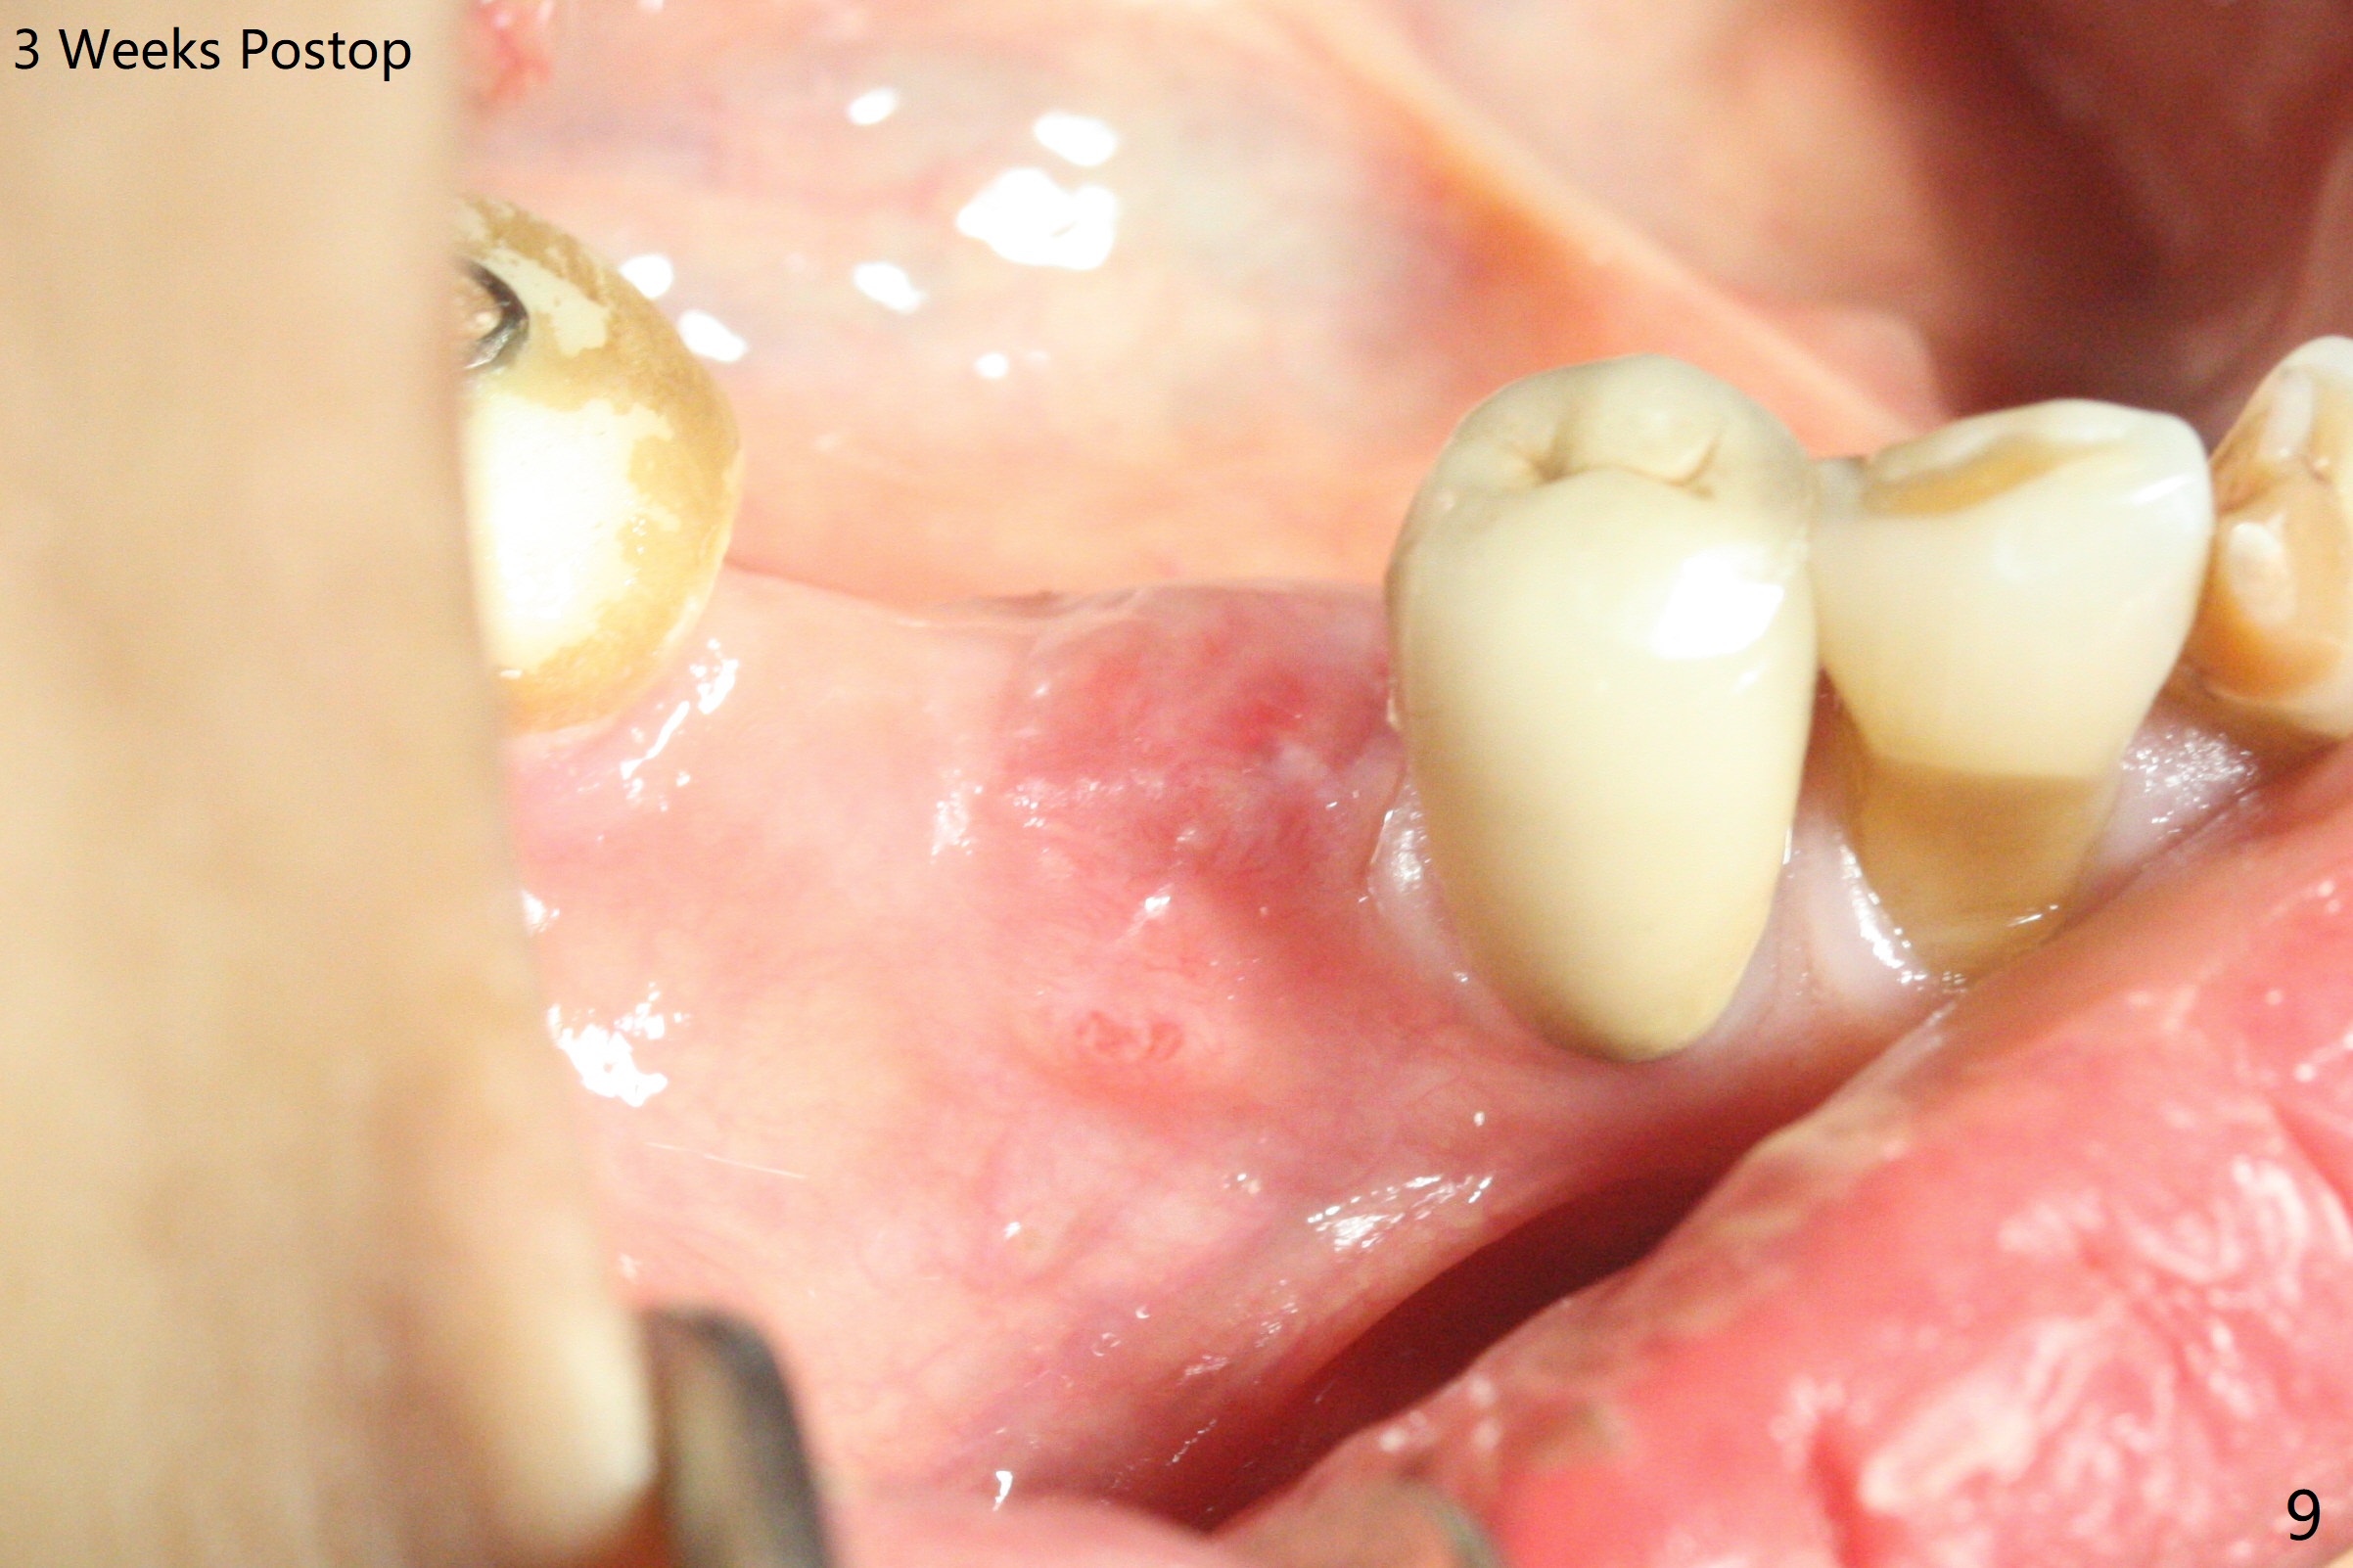

The extraction socket of #31 has a thin septum (Fig.2), which is removed partially with 12 mm bone trimmer (Fig.3). After placement of a 5x9 mm FC implant (~40 Ncm) and 6 mm bone profile drill, a 5.5x4(2) mm abutment is incompletely seated (Fig.5 <) and later is changed to a 4.5x1 mm temporary abutment (Fig.6, 8 T). The latter is used to fabricate a provisional, which in turn supports the distal papilla (Fig.8 *). The gingiva is slightly erythematous immediately post periodontal dressing removal (3 weeks postop, Fig.9). Take CT to confirm whether the cortical drill helps keep the #29 implant lingual. Use a profile drill at #29 if crestal bone loss is not obvious. There is bone coronal to #29 implant 4 months postop (Fig.10). Upon incision, the ridge is rounded (Fig.10'), but the implant appears to be buccally placed (Fig.10'' (post high speed handpiece and 5.5 mm profile drill)). The latter is confirmed by CT (Fig.12, as compared to design (Fig.11)). In spite of use of cortical drill coronally, the implant is still deviated buccally due to contrasting deferential bone density linguobuccally (Fig.13). By comparison, there is no such bone density differential involving an immediate implant at #31; the implant is placed in the socket without contacting the buccal or lingual cortices (Fig.14). The final implant is the same as expected (Fig.15). To avoid implant deviation in the lower premolar region, leave the root in place until osteotomy is finished. Five months postop, the temporary and healing abutments at #31 and 29 change to pair ones (Fig.16). Since there is limited clearance from the crestal bone, smaller abutments are used with the apparently same degree of seating (Fig.17). The abutments are prepared due to the mesial (#31) and buccal (29) tilt before impression.